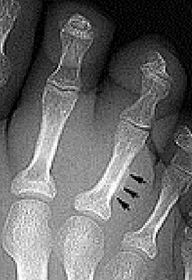

| Describe the alignment of metatarsal 2 | There is no angulation nor displacement of the distal segment relative to the proximal segment. |

| Describe the alignment of metatarsal 3 | The distal segment is displaced laterally (50% apposition) and angulated medially. |

| Describe the alignment of metatarsal 4 | The distal segment is displaced laterally (75% apposition) but there is no apparent angulation. |

| Describe the tubulation of the metatarsals | Metatarsals are overtubulated - decreased girth. |

| Describe the tubulation of the metatarsals | Metatarsals are undertubulated - increased girth. |